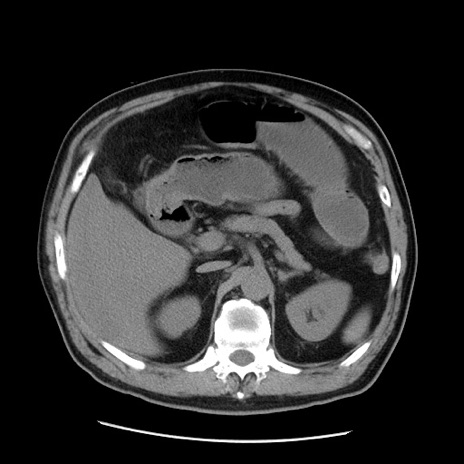

症例20(横断像)

【症例】 60歳代男性

【主訴】 腹部膨満、嘔吐

【現病歴】5日前頃より倦怠感を認め食事量減少し4日前の朝嘔吐、食事摂取困難となった。 3日前近医受診し点滴施行され整腸剤などを処方された。 当日他院を受診し、腹部膨満著明、炎症反応の上昇(CRP10.8、WBC11200)あり、紹介受診となる。

【身体所見】 意識JCS1 受け答えがはっきりしないBP 111/57mHg、 P 67bpm、、BT35.2°C、SpO2 97%(RA)、 腹部:膨隆、打診で鼓音あり、全体的に圧痛有り、腸蠕動音(-)、反跳痛ははっきりせず。

【データ】WBC 11400、CRP 14.20